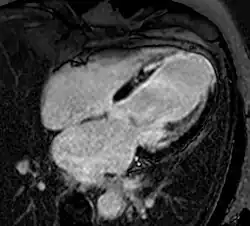

Atrial septal defect with dilation of the right ventricle by CMR

Enlarged right ventricle with poor function in a patient with repaired tetralogy of Fallot by CMR